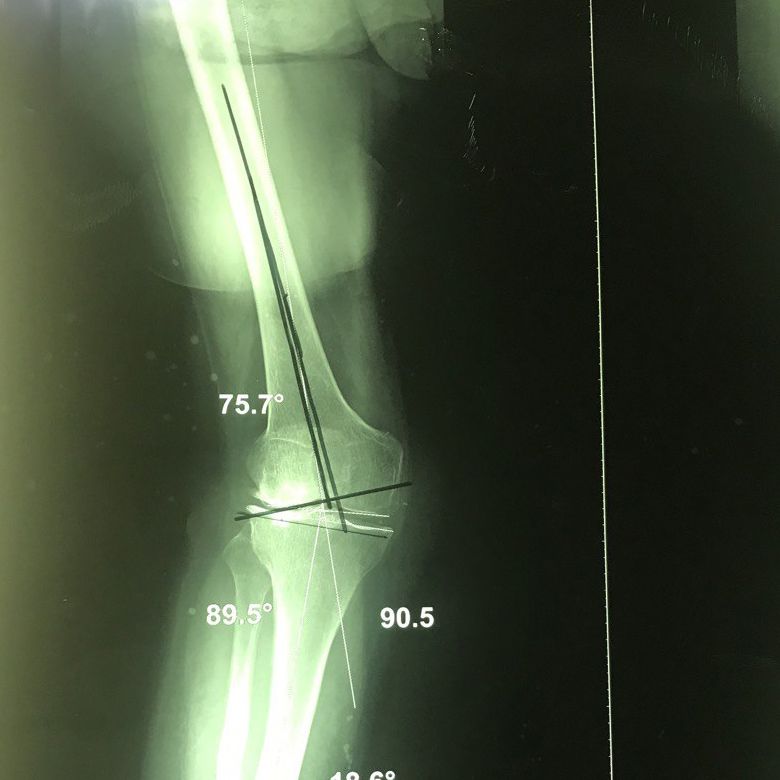

Dizde eksenel sapma

Diz aksiyel deviasyonu dizin yapısal bozukluklarından biri olup, dizde parantez veya çaprazlama şeklinde görülebilir.